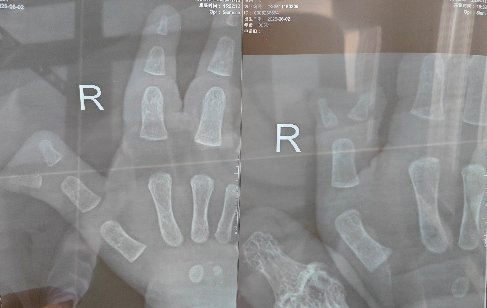

●拇指多指典型表现:多在拇指桡侧、尺侧或两侧多出1~2个拇指,大小通常小于正常拇指(桡侧多出的手指往往更小),还常合并关节面倾斜、三节指骨等其他畸形,需通过X线明确骨骼发育情况;

图源:科室提供